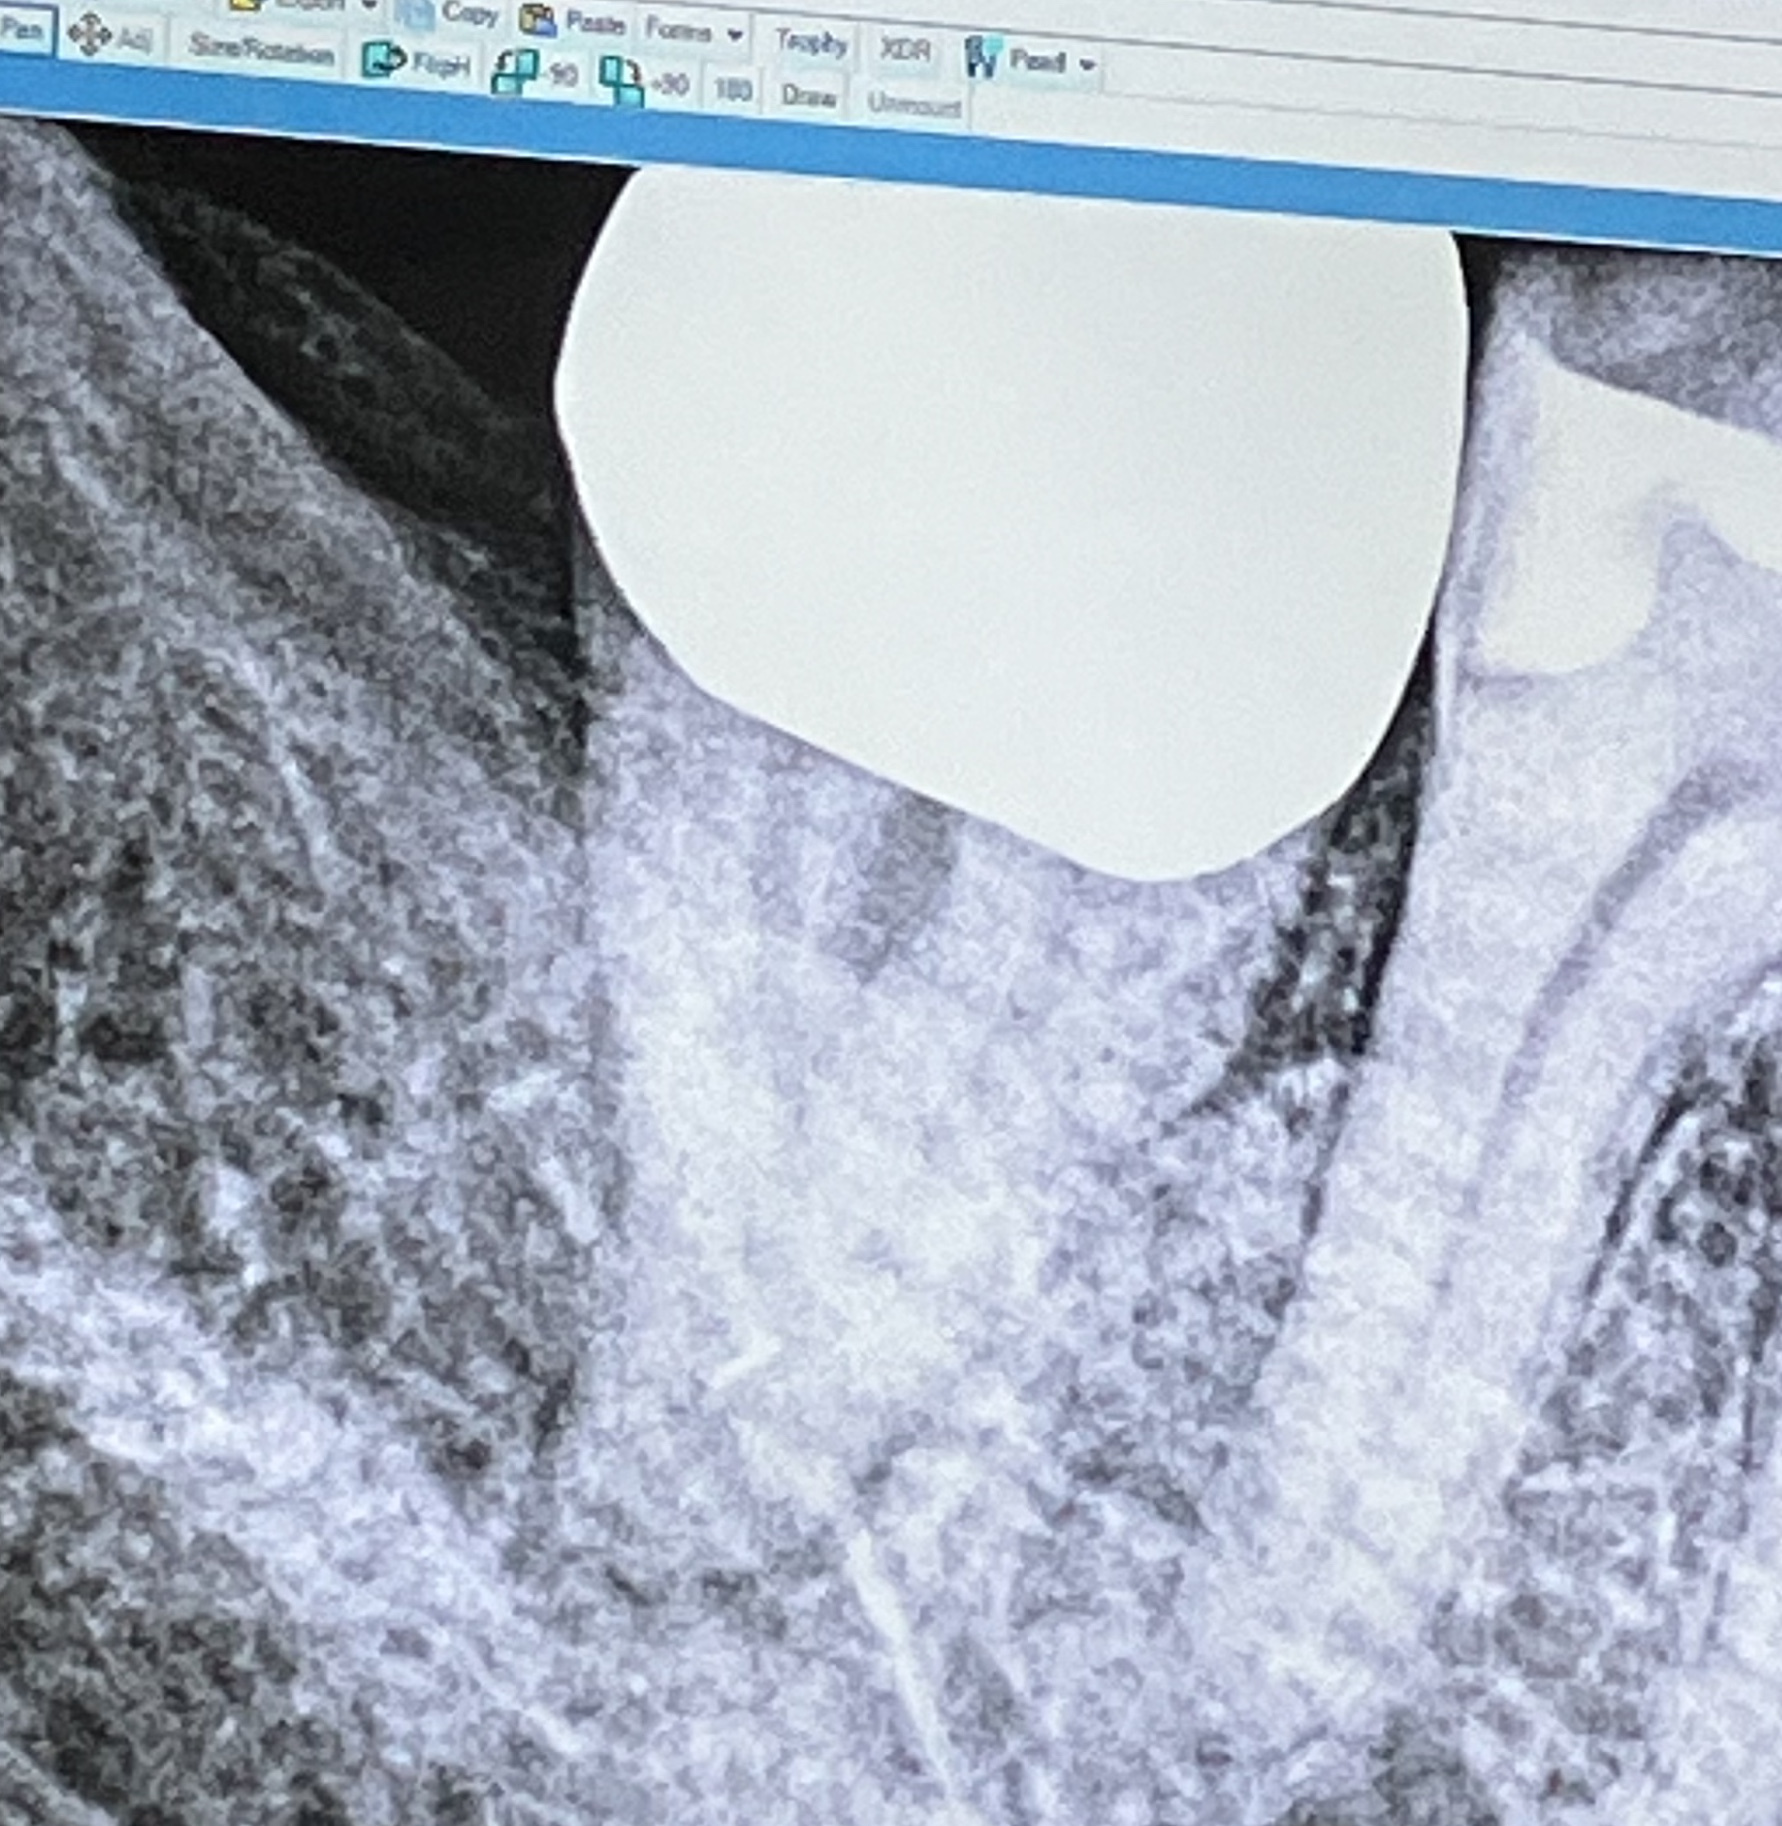

Russ, it’s been a few days so here’s where I’m at now. I have a my first appointment with the oral surgeon tomorrow. One of the things I will be mentioning if he doesn’t mention it first is that on another forum (actually chatGPT which my daughter says is unethical) I’ve read that while ORN is somewhat rare with odds that run from 2 to 28%, a root canal can reduce those odds to less than 1%. The tooth in question isn’t really that bad. It does have a crown that I’ve always thought was too high (if that makes sense). That’s why I went with extraction in the first place, and of course the cost difference,so I thought just get it out! But, if the oral surgeon agrees maybe I’ll go that route instead. Whatever, I’ll take his advice. Oh, by the way I contacted the medical group my RO was at and they sent whatever records they had. Unfortunately they didn’t list the strength of the radiation. I did track down the RO at her new group, gave her a call and while she couldn’t give me the exact strength said for my 31 rad treatments it would’ve been between 6000 and 7000 centigrays (60 to 70 Gy?) so at least I can let the dental docs know. I’ll know more after tomorrow.

Consultation with an oral surgeon yesterday. After discussing the options: 1.) Take a chance with extraction without HBOT. 2.) 20 HBOT dives before extraction, 10 after. 3.) Root canal, avoiding the bone, thus further reducing the chances of ORN. I asked *what if I get the root canal and still need to get it pulled later? Am I wasting my money? He said *not necessarily, it would be delaying it for awhile, might never get to that point. (The tooth itself is salvageable). So Root Canal it is! We’ll see how it goes. (Honestly, if I’d never heard of ORN, the tooth would’ve already been gone. And the cost was a factor at that time: $400 for extraction, $2000 for root canal.) Wish me luck!

It seems the records have mostly disappeared. The radiation oncologist (and her entirely practice) lost their lease and were evicted from the building they occupied about a year after my radiation was complete. I even had a follow up appointment canceled. I reached the medical group she was with and they sent me what was basically a summary of my last visit. It included the history of how many sessions I had and dates, but no strength (rads) were listed. I tracked down the oncologist who is now with a different medical group and gave her a call. Of course she didn’t have the records with her but when I reminded her that I’d had 31 sessions, she said it would’ve been between 60 & 70Gy. I’d never heard of ORN or HBOT until I found it here, on this forum, about 3(?) weeks ago.(Nobody explained any of this **** before hand so yes, I am pissed!) — I took this information to an oral surgeon experienced in this and he gave me three options: Take my chances and pull the tooth — Twenty HBO dives, pull the tooth, ten more dives — If the tooth itself is salvageable (it is) go for a root canal and avoid disturbing the bone, thereby reducing the chance of ORN. I’m getting a root canal on Tuesday. We’ll see how it goes.

Logan, Thanks for your comment. I had my root canal this past Tuesday. It went well except for a minor complication(?) in that the tooth had a weird root configuration, can’t remember what she called it but the two roots kind of crossed each other effectively making three canals. The endodontist had a hard time seeing it (another question mark here because I really didn’t understand her) but she finally got it all taken care of. I’m going back for a follow up on Tuesday just to see how I’m doing. But it is a relief that it’s basically done! Oh, I was worried that I’d have to go back to my dentist for a new crown but the endodontist went right thru the existing one without breaking it which sometimes happens, a small filling in the hole and I’m good to go. When I go to my follow up on Tuesday I will verify with her that nothing more needs to be done.